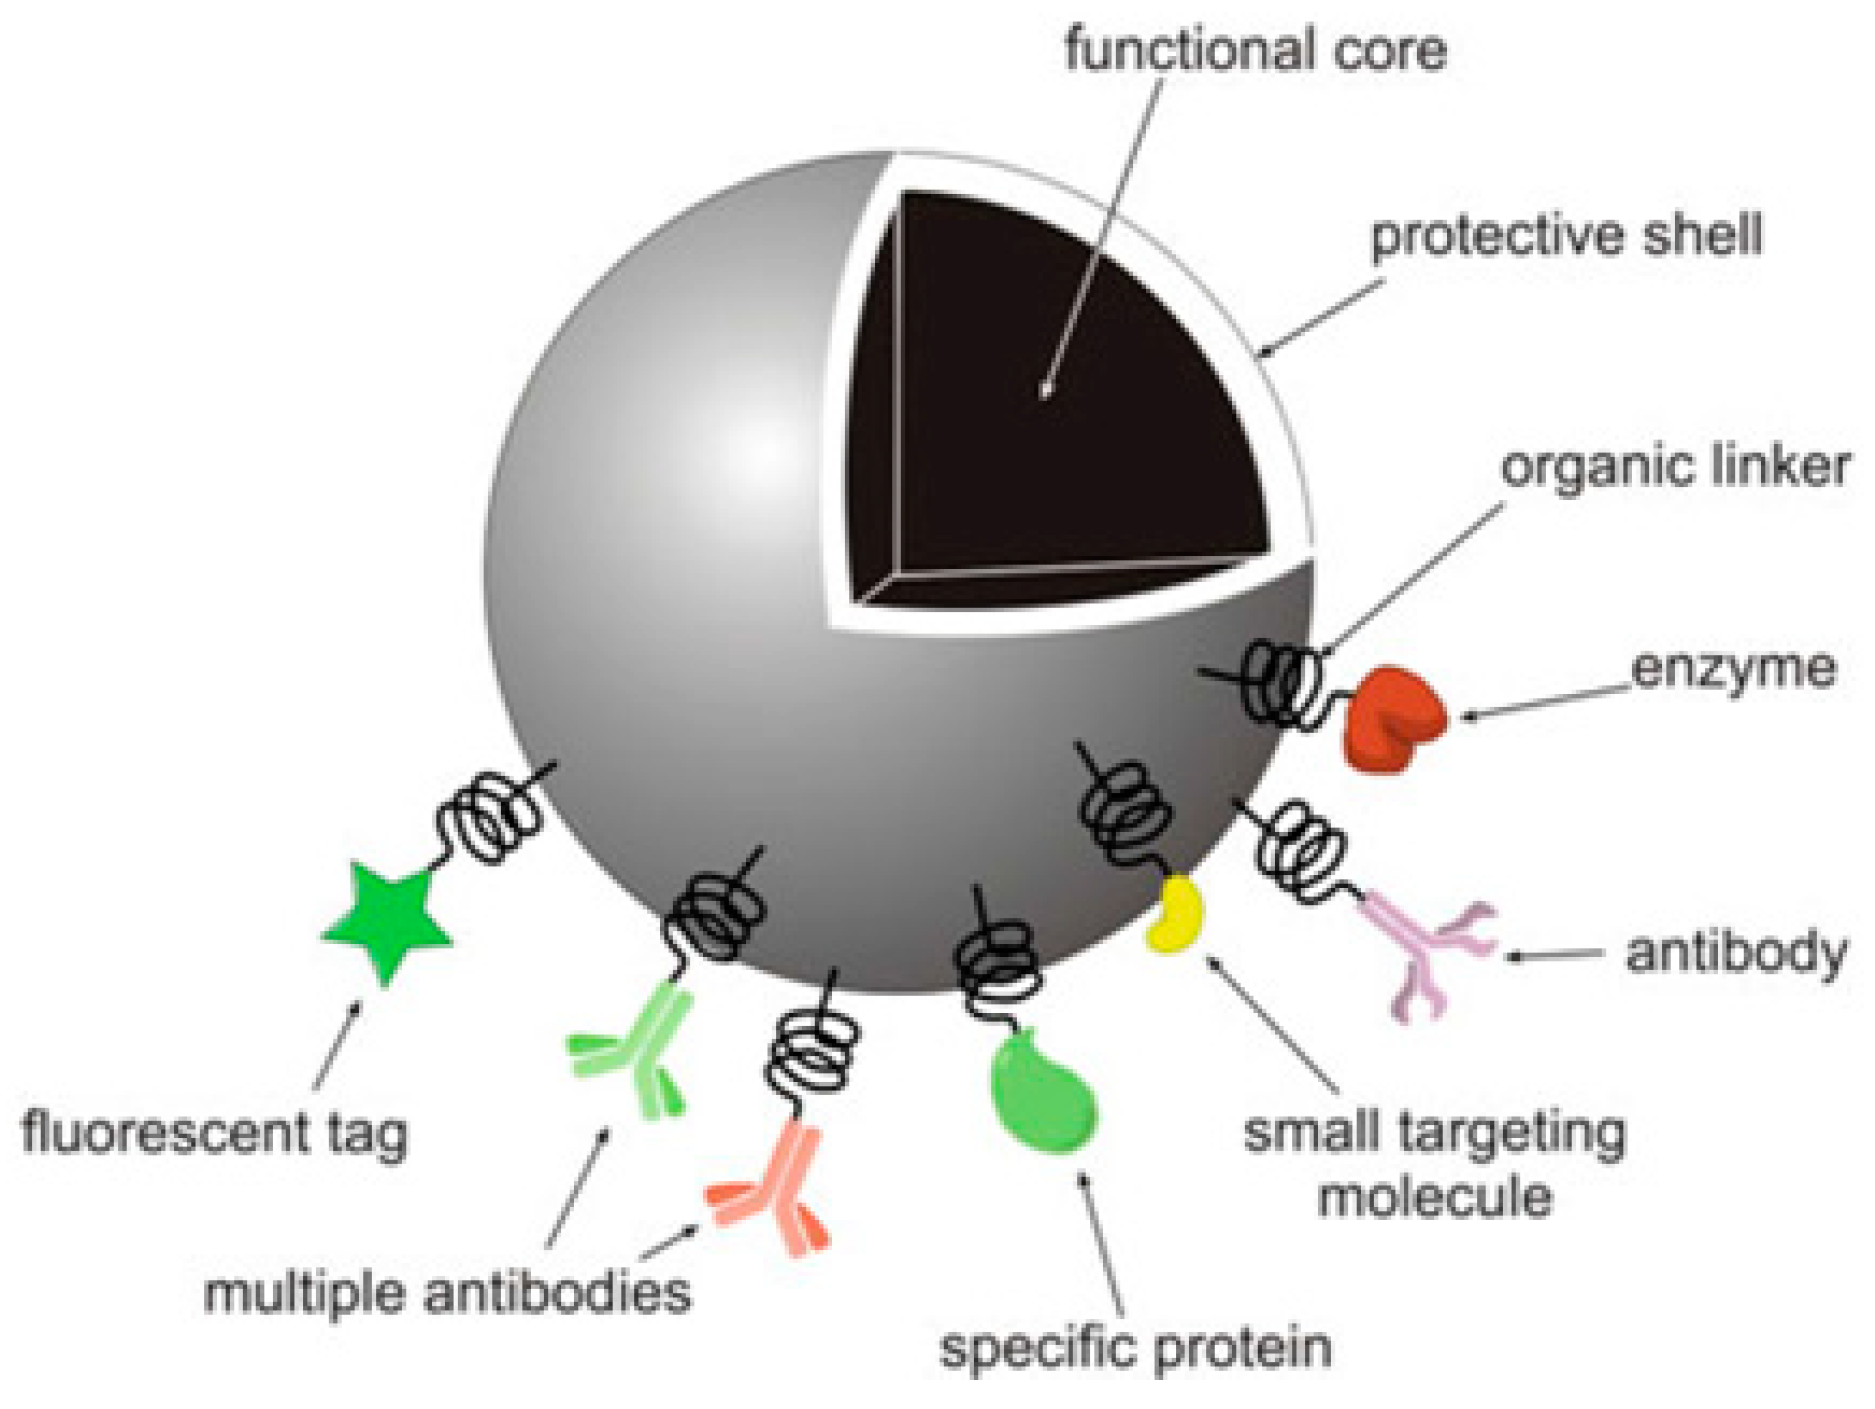

1.1. Why Nanoparticles?

2. Drug Delivery System

2.3. Mesoporous Silica Nanoparticles (MSNPs)

2.4. Gold Nanoparticles (GNPs)

2.5. Other NPs Used as Drug Delivery Carriers